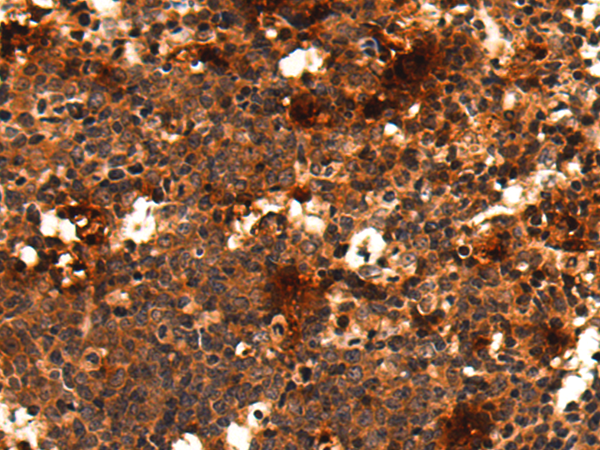

- The image is immunohistochemistry of paraffin-embedded Human colorectal cancer tissue using P03571(TSR1 Antibody) at dilution 1/50. (Original magnification: ×200)

- The image is immunohistochemistry of paraffin-embedded Human thyroid cancer tissue using P03571(TSR1 Antibody) at dilution 1/50. (Original magnification: ×200)